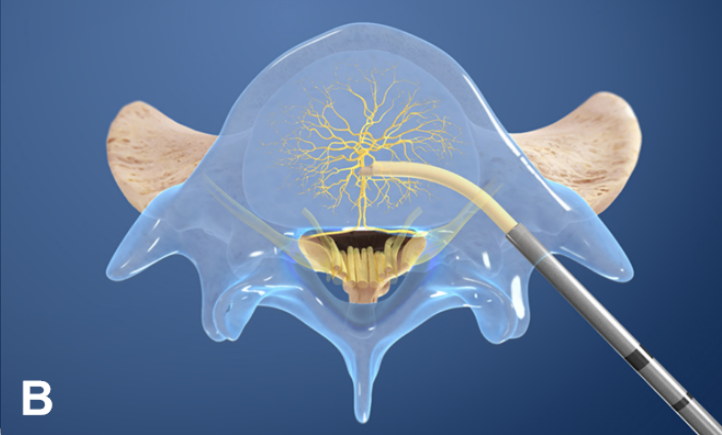

其实,椎体及终板的神经支配主要来自于窦椎神经的分支椎基神经,而椎基神经中 P 物质和 PGP 9.5 呈阳性反应,提示椎基神经可传递疼痛。生理情况下,终板的神经密度类似于外层纤维环。

然而,病变终板的神经密度明显高于无病变终板和病变的纤维环。

左图为正常的纤维环和终板神经支配情况,右图为病变的纤维环和终板,可见神经末梢向深层长入。

理论上讲,任何接受神经支配的腰椎及其相邻的软组织结构都可能是腰痛的起源部位。因此,Modic 改变有引起腰痛的解剖学基础。

③经皮内镜下硬膜外椎基神经激光消融术

值得关注的是,系列前瞻性多中心随机对照研究和前瞻性观察研究证实椎体内椎基神经射频消融术可有效缓解疼痛性 Ⅰ 型或 Ⅱ 型 Modic 改变患者的腰痛症状,减少阿片类药物的用量,且疗效优于保守治疗。

国际脊柱外科手术学会指南也推荐采用椎体内椎基神经射频消融术治疗 Ⅰ 型或 Ⅱ 型 Modic 改变引起的慢性腰痛。